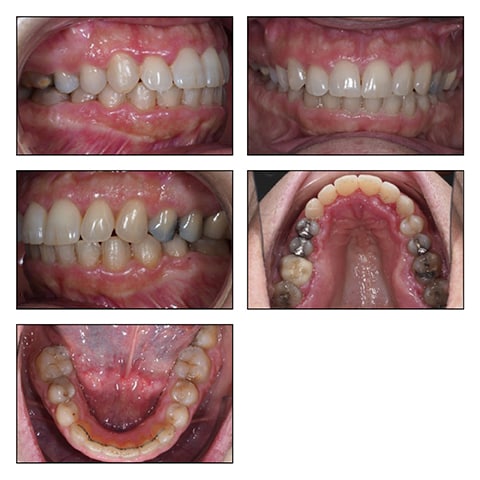

Phase III: Final Inter-Digitation of the Dental Arches. Finishing.

During finishing (0182x0182 Beta III Titanium) the patient wore Inter-maxillary elastics. See Figure 4A-E

Figure 5A-D, Figure 5E-I, Figure 5J

The final cephalometric analysis and the structural superimpositions show an incredible anterior mandibular auto-rotation with a counter clockwise movement of the face, the mandibular plane and the occlusal plane leading to a skeletal and bite closure.

Within the sagittal skeletal patterns, the slight proclination of the incisors after treatment helped to get an ideal overjet/overbite and an improvement of the profile. (Table 4-2)